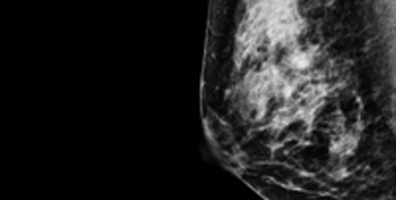

The Breast Imaging section of Diagnostic Radiology offers a full range of services. Breast imaging services include 3D screening and diagnostic mammography, breast ultrasound, magnetic resonance imaging (MRI), and interventional procedures. The multidisciplinary breast center is located on the 9th floor of the Center for Health and Healing 2.

Fellows spend the year in the OHSU breast imaging center, receiving clinical training in digital breast tomosynthesis, breast ultrasound, breast MRI, and all associated interventional techniques including aspiration, steroid injection, biopsy, and preoperative localization.  The weekly schedule includes time on diagnostics, screenings, interventions, MRI, interpretation of outside imaging, and academic time.

The breast center is located in the Center for Health and Healing building 2 at the South Waterfront campus and opened in the spring of 2019. The breast center is located adjacent to the breast surgery and breast oncology clinics, for close collaboration. The center has 4 Hologic mammogram units, an upright Affirm mammography biopsy unit and 2 dedicated breast ultrasound rooms. MRI’s are performed on 1.5 and 3T scanners. The reading rooms have screening and diagnostic pods with Visage PACS reading stations.